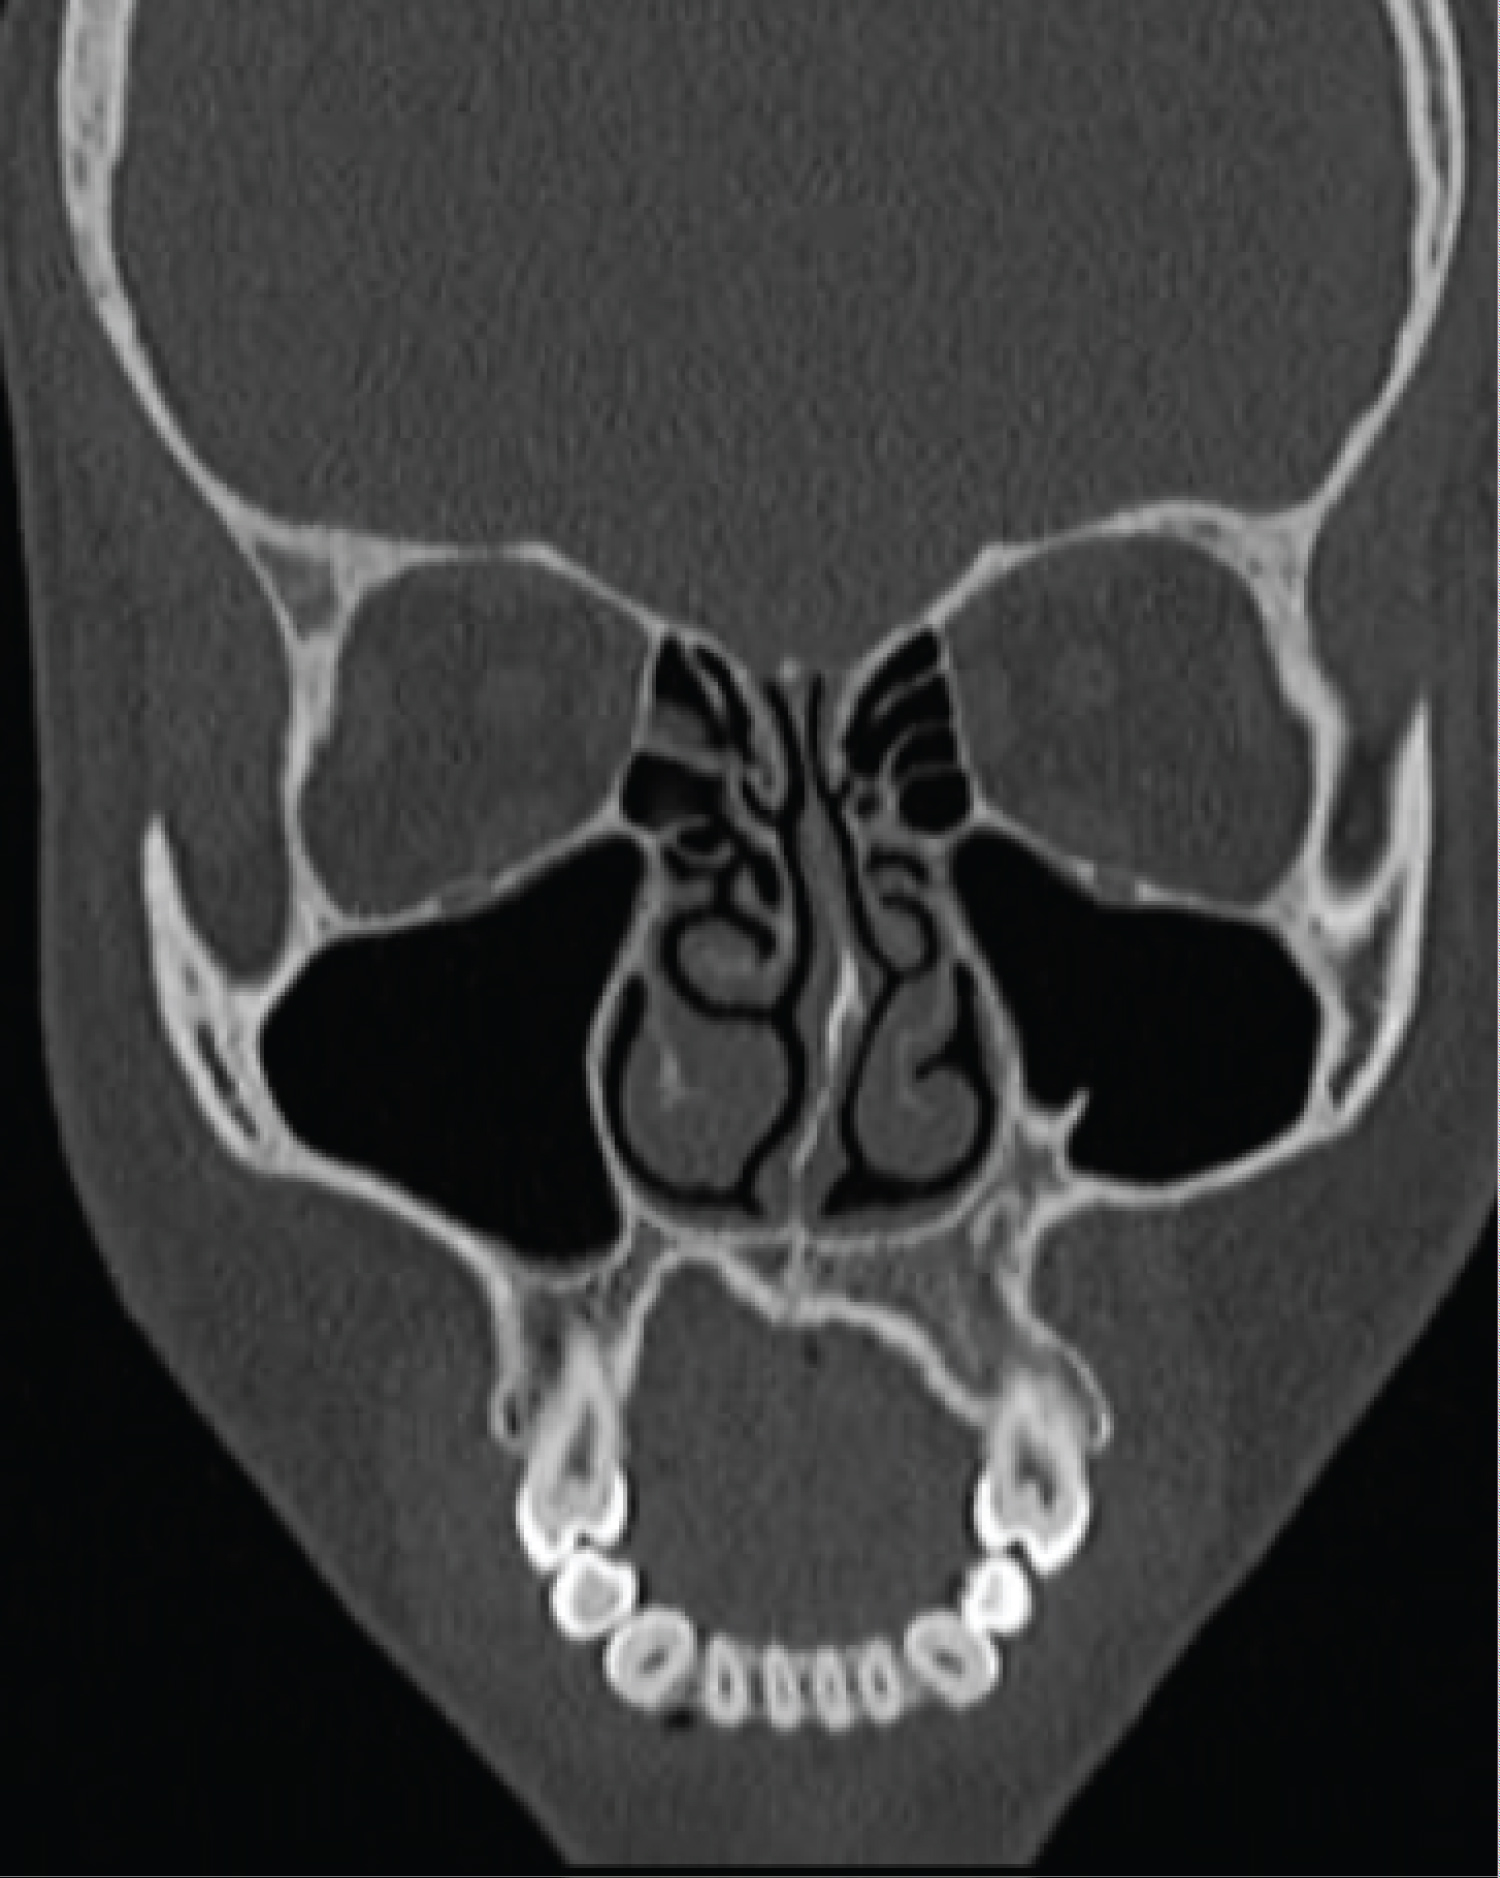

In the computed tomography was observed a 4 cm hypodense, unilocular, well-defined and non-invasive image located on the left maxilla. A hyperdense image, compatible with unerupted left canine was noted within the lesion (Figure 1), and displacement of the maxillary sinus.

Figure 1: Hyperdensity within unilocular well-defined hypodense image on the left maxilla. View in a coronal section. View Figure 1